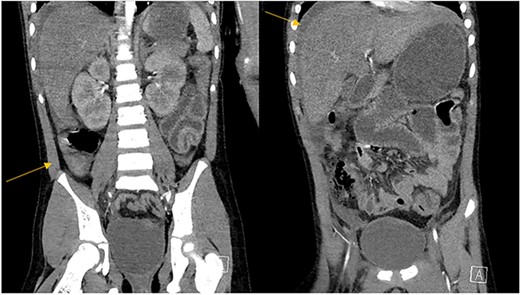

The patient was an 8-year-old female who presented to hospital with a 3-day history of fever, abdominal pain, and coffee ground emesis. On presentation, she was afebrile, tachycardic, and hypotensive. On examination, she had an acute abdomen and septic shock. Initial laboratory investigations revealed a venous pH of 7.08, CO2 of 47 mmHg, bicarbonate of 14 mmol/L, lactate of 3.9 mmol/L, white blood cell count of 3.7 × 109/L with an absolute neutrophil count of 0.96 × 109/L, C-reactive protein of 389 g/L, INR of 1.7, PTT 36 s, fibrinogen of 5 g/L, and an acute kidney injury with a creatinine of 100 micromoles/L and urea of 10 mmol/L. An abdominal ultrasound revealed a starry sky appearance of the liver with moderate free fluid in the right upper quadrant. She was not fluid-responsive and thus was treated with an epinephrine infusion and empiric antimicrobial therapy with ceftriaxone and vancomycin. Transportation was arranged to a tertiary care center with access to pediatric intensive care and surgical services. In transport she developed mild erythema to the right calf with severe pain to palpation and dorsiflexion out of proportion of clinical findings (Fig. 1). Her creatine kinase level was 10 000 U/l and a computerized tomography (CT) scan of the right leg demonstrated extensive soft tissue gas and myonecrosis (Fig. 2). An abdominal CT scan demonstrated evidence of bowel perforation in the right lower quadrant with associated loculation, intra-abdominal free air and fluid, and proximal bowel dilation (Fig. 3). Considering these findings, antibiotics were broadened to piperacillin-tazobactam, vancomycin, and clindamycin, and she was urgently taken to the operating room.

Abdominal CT scan demonstrating intrabdominal free fluid and a collection in the right lower quadrant.